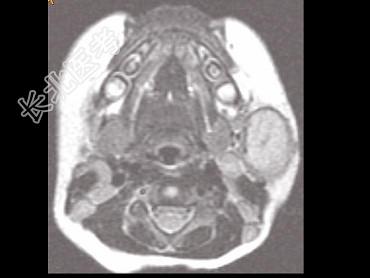

- 单项选择题男,40岁, 左面部渐进性增大的包块,MRI检查如图所示, 最可能的诊断是 ( )

A、左面部毛细血管瘤

B、左面部囊肿

C、左面部脓肿

D、左面部脂肪瘤

E、左面部神经纤维瘤